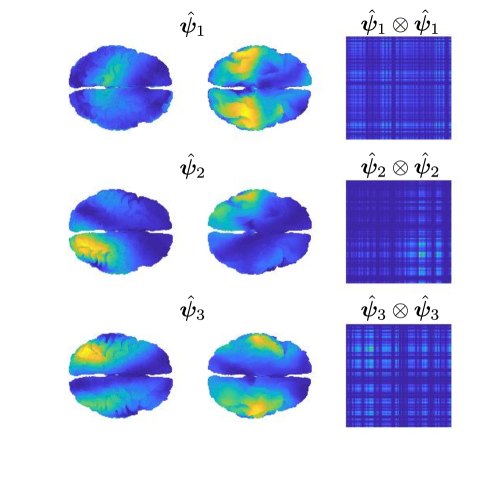

A regularization parameter common to all the PC components is chosen by inspecting the plot of the regularity of the first PC covariance functions () versus the residual norm, for different choices of the parameter. This is a version of the L-curve plot (Hansen, 2000) and is shown on the left panel of Figure B.2. Here we show the results for , in the appendices we show the results for . The energy maps of the estimated , and resulting from the analysis are shown in Figure 11. These are associated with the first three PC covariance functions , and . High intensity areas, in yellow, indicate which areas present high average interconnectivity, either by means of positive or negative correlation in time.

In Figure 12, we show the plot of variances associated with each time segment, describing the variation in time of the PC covariance functions, hence the variation in interconnectivity. The variance can be either defined on the sensors space, by normalizing the PC covariance functions , with the forward operator, or on the brain space, by normalizing the PC covariance functions on the brain space . Due to the presence of invisible dipoles, which are dipoles that display zero magnetic field on the sensors space, the two norms can be quite different, leading to different average variances for each PC covariance function. Due to the high sensitivity of the source space variances on the choice of the regularization parameter, we focus on the estimated variances on the sensors space.

In Figure B.3-B.4 we show respectively the plots of the estimated PC covariance functions and associated variances from the dynamic functional connectivity study on segments with regularization parameter .

In Figure B.5-B.6 we show the estimated PC covariance functions and associated variances from the dynamic functional connectivity study on time segments with regularization parameter .